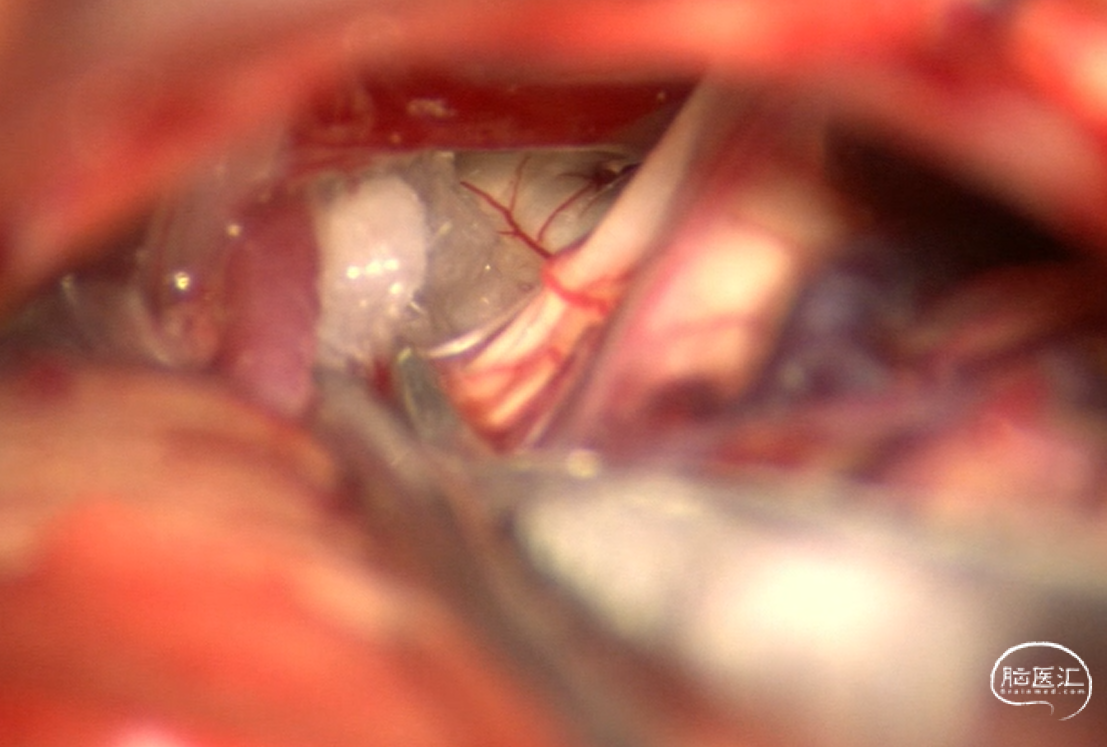

手术过程:常规乙状窦后入路准备,侧卧位,乳突后发迹内直切口,约6cm,暴露星点后于其前下方颅骨钻孔,铣刀游离骨瓣,磨钻扩大骨窗到达乙状窦后缘,骨窗直径约3cm,硬膜外止血满意(确保剪开硬脑膜后术区为无血状态)后T形切开硬脑膜并悬吊,窄脑压板牵开小脑后释放脑脊液脑压下降满意后于后组颅神经处剪开蛛网膜进一步释放脑脊液,分离小脑绒球与后组颅神经粘连,在面听神经和后组颅神经间可见粗大椎动脉走行面神经REZ区,抬起椎动脉后见小脑前下动脉紧贴于脑干及面神经,将椎动脉及小脑前下动脉分别给予Teflon垫棉隔离,此时电生理提示LSR仍部分存在,调整头位及显微镜角度后见内听动脉沿面神经腹侧走行,小心分离,无明显穿支血管,给予垫棉隔离后电生理提示侧方扩散波消失。术区反复温生理盐水冲洗,止血满意后水密缝合硬脑膜,必要时用肌肉/筋膜修补缝合,骨瓣用连接片固定复位后逐层关颅,避免各层间死腔。患者清醒后未见面部 抽搐。

垫起椎动脉和小脑前下动脉后仍有LSR存在

调整头位及显微镜角度后发现,內听动脉走行于面听神经复合体腹侧,垫起内听动脉后LSR基本消失: